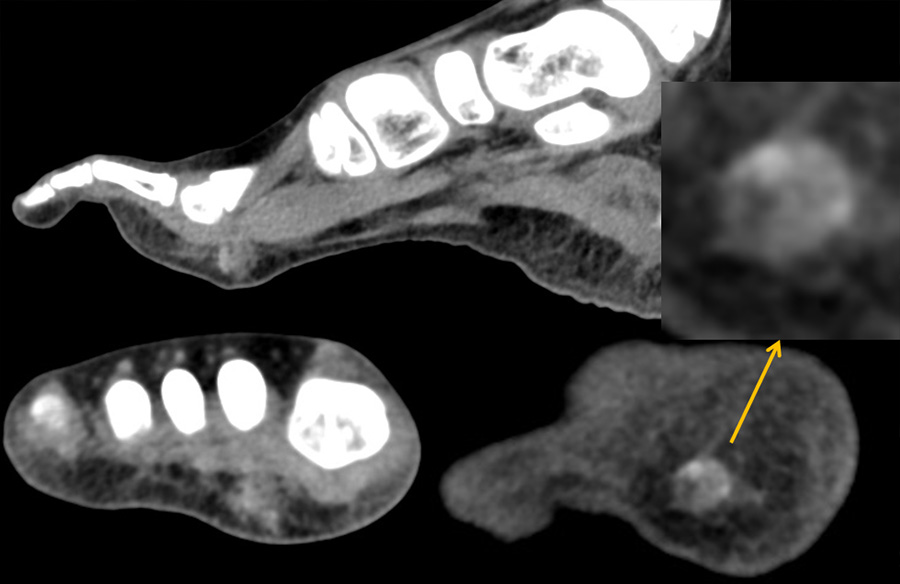

8歳男児 歩行時痛、足底部腫瘤

FST2WI sag

T1WI

FST2WI

Dynamic FST1WI

- 【参考症例】

- 【石灰化腱膜線維腫 Calcifying aponeurotic fibroma】

- 手掌、足底、手/足首に好発(腱、腱膜、筋膜)

- 小児に発生(median 12歳)

- 良性、局所浸潤性

- 通常 < 3 cm

- 局所再発は最大 50%

- 画像では浸潤性の軟部腫瘍、結節状石灰化、強く不均一な増強効果